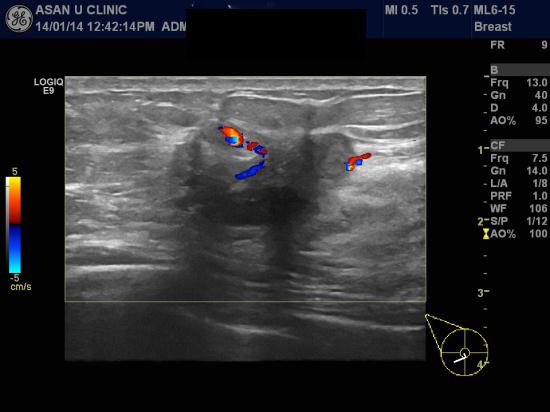

아산유외과 개원 후 57번째 유방암 진단.

건강검진상 이상소견있어 의뢰되신 46세 여성분입니다.

우측유방에 2.6cm이상의 종괴와 겨드랑이 부위에 림프절이 커져있어

조직검사하였으며

유방의 침윤성 유관암, 우측 겨드랑이 림프절에 전이암 소견 확인하였습니다.

40대후반 여성은 유방암으로 진단되는 발생률이 가장 높아서

건강검진으로 유방암검진 결과를 꼭 다시한번 확인해보시길 당부드립니다.